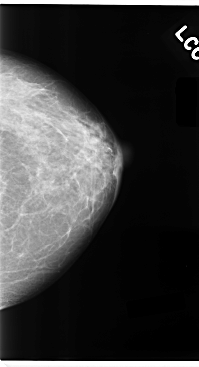

C_0100_1.LEFT_MLO

C_0100_1.LEFT_CC

LEFT_MLO LINES 4704 PIXELS_PER_LINE 2664 BITS_PER_PIXEL 12 RESOLUTION 50 NON_OVERLAY

LEFT_CC LINES 4760 PIXELS_PER_LINE 2576 BITS_PER_PIXEL 12 RESOLUTION 50 NON_OVERLAY